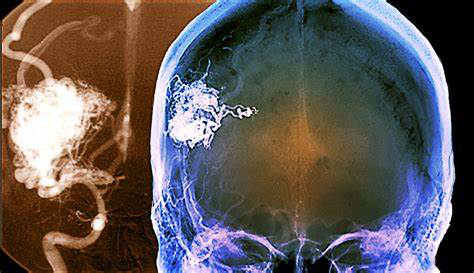

脑动静脉畸形(AVM)在破裂出血前往往没有症状。一些患者确实出现了没有破裂的症状——这往往发生在中年,男性比女性略多。症状的严重程度可能差异很大;在一些人身上,身体变得衰弱甚至威胁生命。

癫痫发作和可能严重的头痛是动静脉畸形较普遍的症状,但没有发现特定类型的癫痫发作或头痛模式。癫痫发作可以是局灶性的(意味着它们涉及大脑的一小部分)或全身性的(广泛的),包括抽搐、对运动失去控制或一个人意识水平的变化。头痛的频率、持续时间和强度差异很大,有时会像偏头痛一样严重。疼痛可能在头的一侧,也可能在两侧。有时,持续影响一侧头部的头痛可能与AVM病的发病部位密切相关。较常见的是,疼痛的位置并不特定于畸形,可能包括头部的大部分。